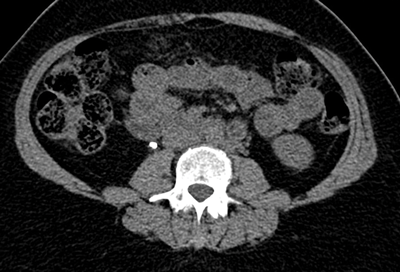

The stone alongside the stent may be masked using abdominal windows, but when changed to bone windows, the stone can be clearly seen due to the difference in HU of the stone compared with the stent (Figure 1) [1].

Figure 1a: Abdominal windows stone and stent.

Figure 1b: Bone windows stone and stent.

This allows a stent or nephrostomy tube to be distinguished from a calculus [2] and can help aid further patient management.